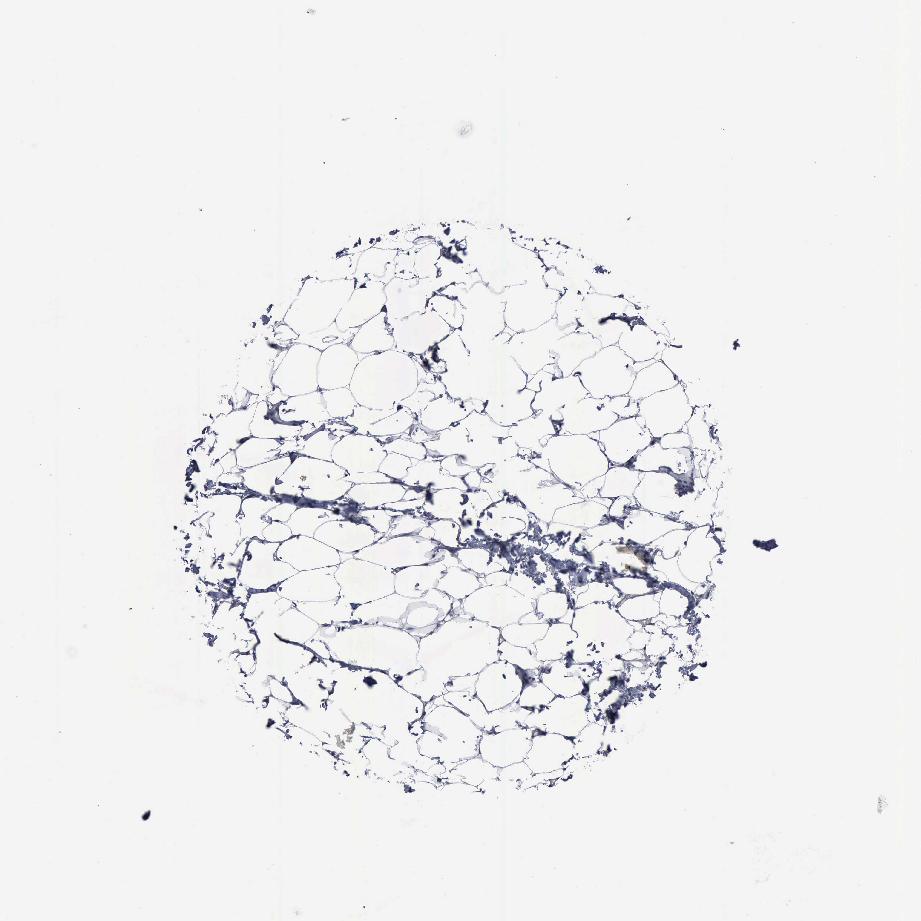

SOFT TISSUE 1 - Antibody stainingi

Antibody staining in the annotated cell types in the current human tissue is reported as not detected, low, medium, or high, based on conventional immunohistochemistry profiling in selected tissues. This score is based on the combination of the staining intensity and fraction of stained cells.

Each image is clickable and will lead to virtual microscopy that enables deeper exploration of all samples and also displays staining intensity scores, fraction scores and subcellular localization as well as patient and tissue information for each sample.

Antibody HPA000807Antibody HPA001063

Fibroblasts Not detectedNot detected

Peripheral nerve -Not detected